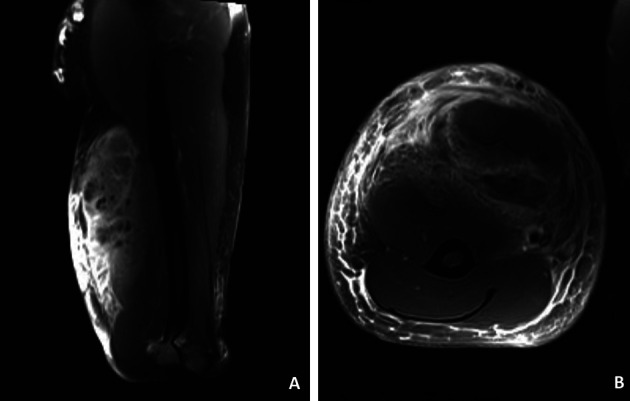

笔者同时对其进行了磁共振成像和超声检查(图2和图3),表明注射材料使二头肌浸润。手术切除受损的组织(图4)。病理检查可见异物巨细胞反应。患者返回原籍国之前未报告进一步的不良反应(图5)。

图2.磁共振成像表现为双侧肌肉组织前室和三角肌肌肉外侧均发生广泛的炎症变化,与肌炎,筋膜炎和蜂窝织炎相适应。脂肪或其他高脂质含量的异物可能与先前注入的异物有关,使前房和三角肌外侧肌组织扩散浸润。A,矢状面图像。B,冠状截面图像